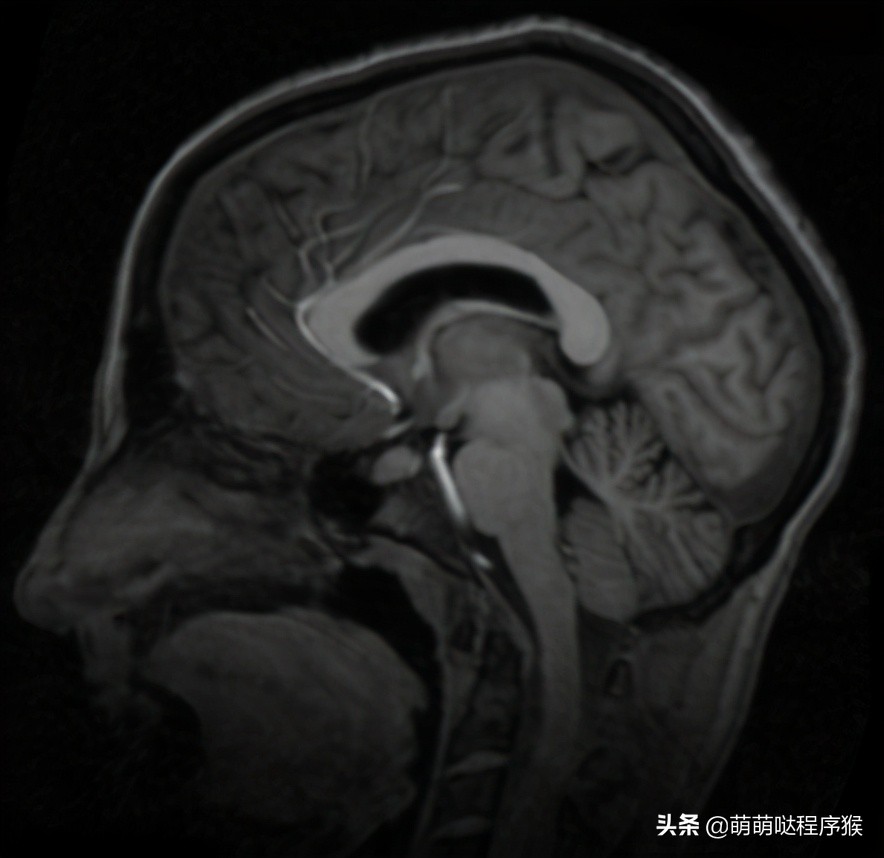

2. 脑部图像配准结果

参考图像

浮动图像

多次迭代过程中浮动图像的变化过程

多次迭代过程中浮动图像与参考图像的差值图变化过程

配准时α参数很重要,通常需要多试几个合适的参数,或者设定一个较小的初始值,随着迭代次数的增加,逐渐增大α值,这样配准效果会更好。高斯滤波参数通常取59*59窗口、10.0的sigma值。迭代次数取50~100次就好了。